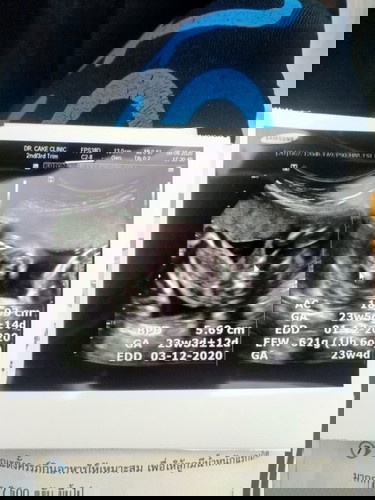

อยากถามแม่ๆว่ากระจู๋จริงๆใช่ไหมคะ จะเริ่มซื้อของแล้วค่ะ อยากได้ความมั่นใจ ☺️

ใช่ค่ะ จู๋น้องแน่นอน